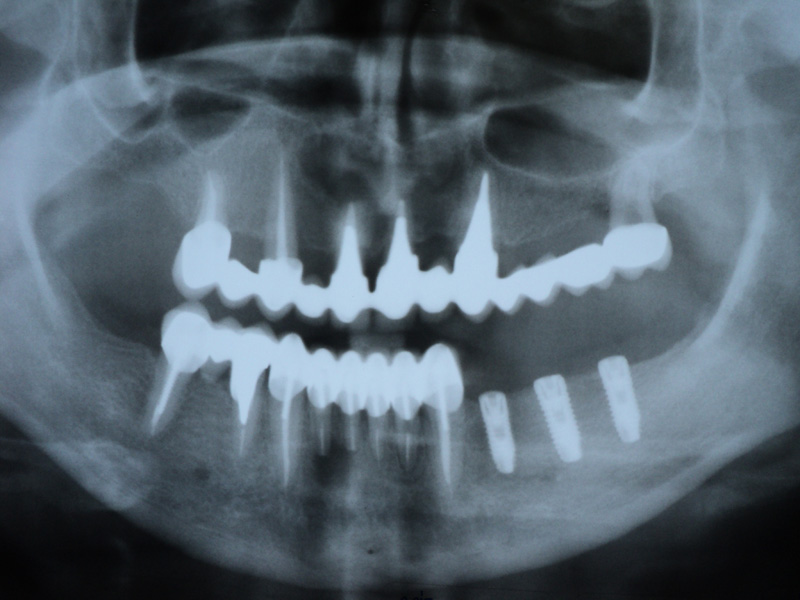

Implante - Galerie Foto

Caz II